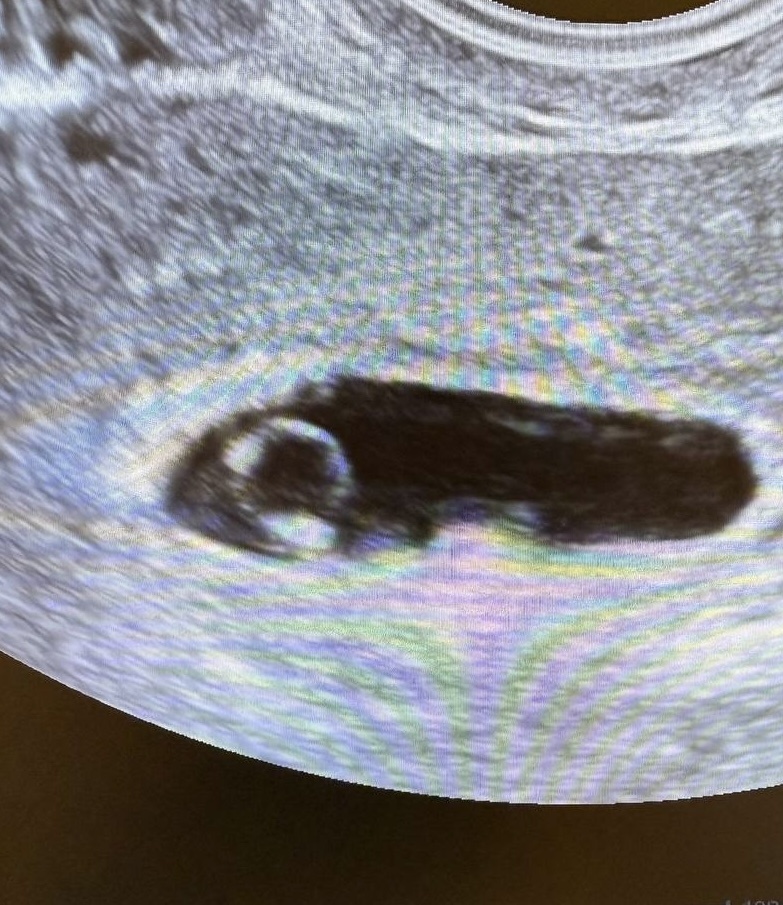

Эмбрион был. И сердечко активно мерцало на экране. Но вот послушать его никак не удавалось, слишком мал он еще был.

Показала пациентке картинку на мониторе в реальном времени, объяснила, что все хорошо, но аппарат пока не может зарегистрировать звучание.

—Кольцо с бриллиантом,- сказала Инна.

—Да, очень похоже.

Беременность 6 недель. Желточный мешок в виде колечка, эмбрион — « бриллиант»